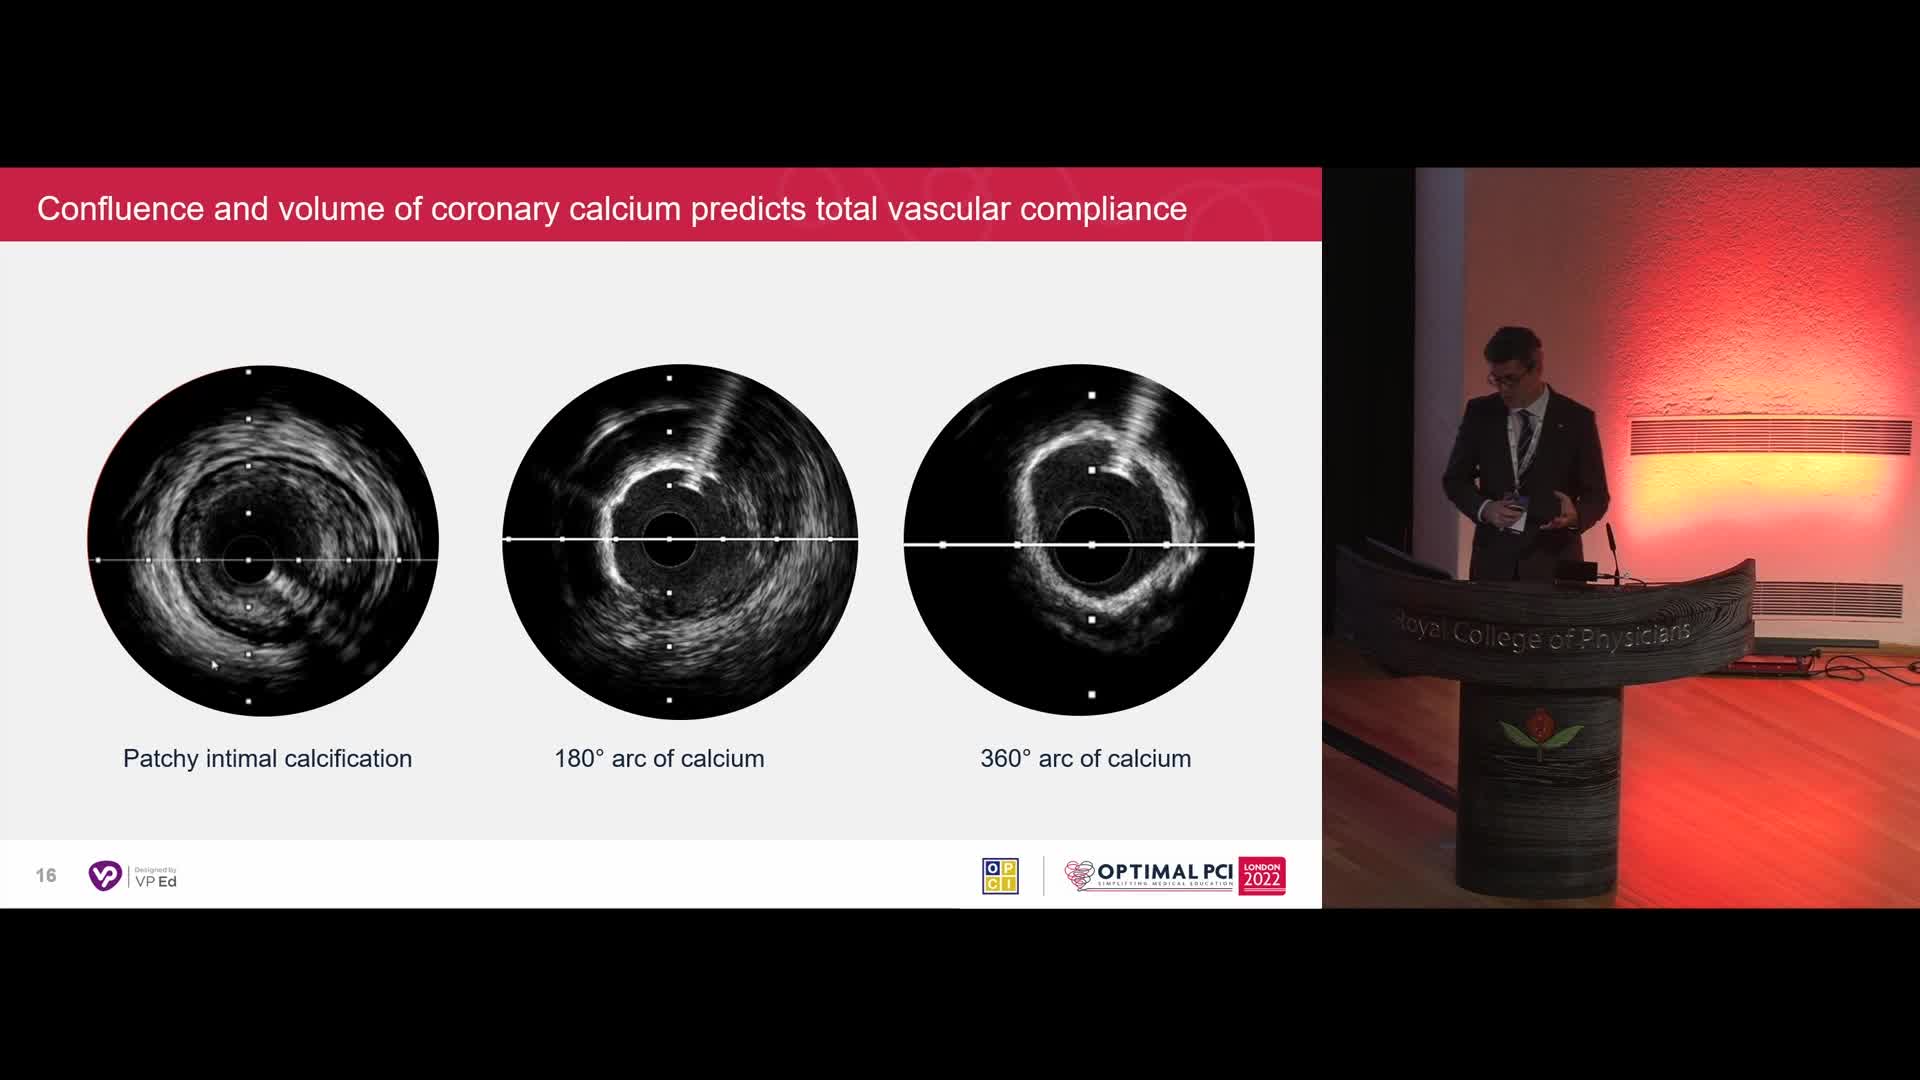

Session 2: Coronary calcium – too hard to crack?

OPTIMAL PCI LONDON 2022 - Day 1

Calcium Masterclass with Shockwave IVL

Treatment of coronary arterial calcium (CAC) has being redefined. We explore the interaction between CAC and patient...